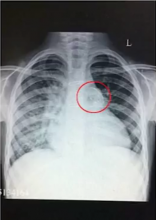

This video shows the replacement of an infected homograft in a six-year-old boy. He had truncus arteriosus repair at four months. The RV-PA conduit was replaced when he was four years old with a homograft. At six, he presented with an intermittent fever that had lasted for eight months. ECHO showed severe conduit stenosis, with possible right pulmonary artery origin. The LPA was possibly occluded by organized vegetation/thrombus. The infected homograft was replaced with a handmade bovine pericardial conduit with 0.1 mm thick PTFE bicuspid valve.